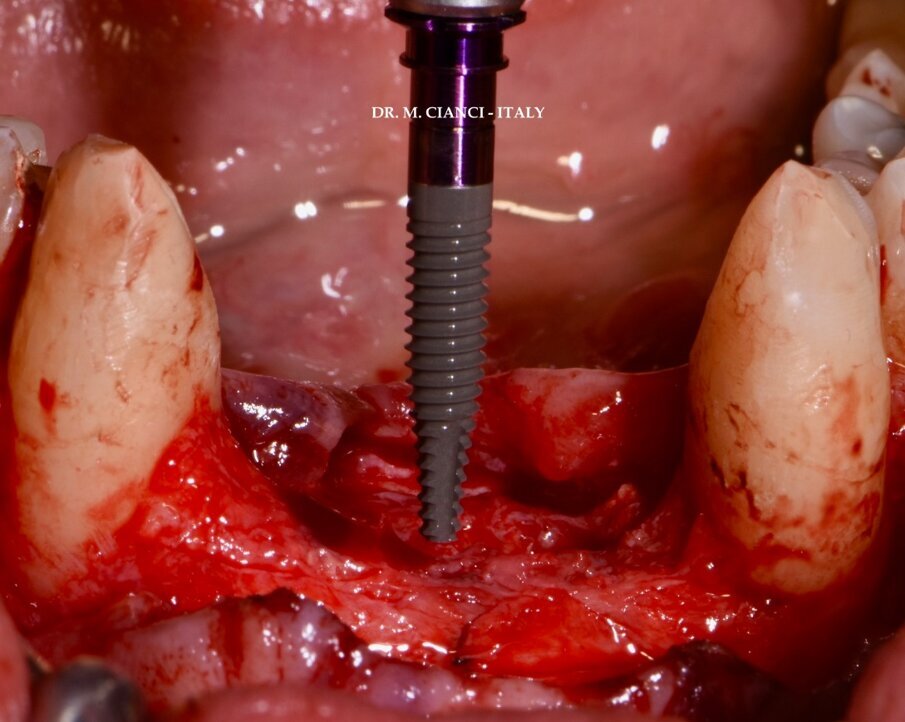

Sei mesi dopo la GBR il controllo tomografico confermava il successo della rigenerazione (Fig. 4) per cui sono stati inseriti 3 impianti narrow Piattaforma 3.0 INTERNA BTI diametro 3.0 mm equamente distanziati tra i due canini: la connessione interna esalobulata (Fig. 5) permette il carico immediato anche con impianti di diametro così ridotto evitando i punti di affaticamento con una buona distribuzione dei carichi assiali, laterali e di torsione4; la superficie implantare UnicCa, ottenuta attraverso una modifica con ioni di calcio e tipica di tutti gli impianti BTI, è una superficie elettropositiva, pulita e super-idrofilica, stimola l’attività osteogenica e promuove la stabilità ossea peri-implantare minimizzando l’aderenza batterica e favorendo la conservazione dei tessuti marginali5-7 (Fig. 6).

Fig. 5 - Impianti BTI Narrow 3.0 a connessione interna esalobulata.

Sollevato un lembo a spessore totale vestibolo-linguale con incisione crestale sono state utilizzate frese di diametro progressivo a basso numero di giri con protocollo di fresatura biologica senza irrigazione esterna a eccezione della prima lanceolata: 1.8 e 1.8/2.5 mm di diametro (75 RPM) al fine di ottenere la stabilità primaria necessaria a eseguire il carico immediato. Tre impianti narrow 3.0 x 13 mm INTERNA sono stati inseriti equidistanti con un torque di 50 Ncm con posizionamento della piattaforma protesica, come da protocollo Dr. E. Anitua, a livello iuxtacrestale (Fig. 5).